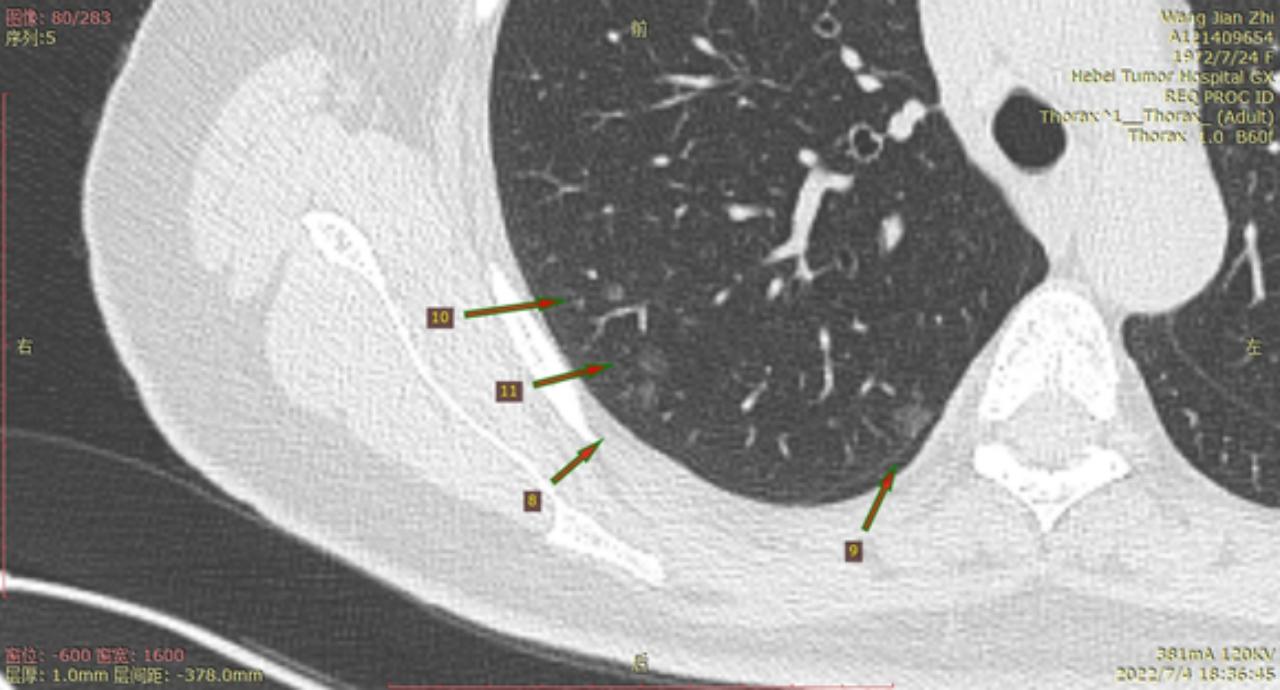

结8-11